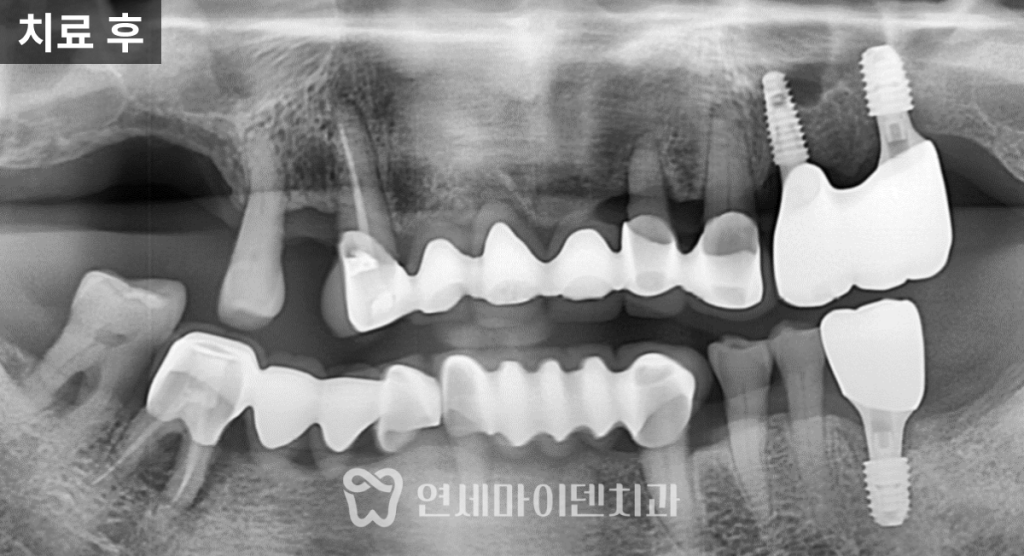

임플란트를 마무리한 이후,

어머님은 해당 부위로 다시 식사가 가능해졌습니다.

치료 전에는 한쪽으로도 식사가 쉽지 않았지만,

치료 후에는 음식물을 씹는 데

큰 불편이 없다고 말씀하셨습니다.

6개월 이상 경과 관찰에서도

상태는 안정적으로 유지되고 있으며,

위생 관리 방법에 대한 교육과

정기적인 체크업을 병행하며 관리 중입니다.

반대쪽 치료도 시기를 조율하며

치료 계획을 세워둔 상태입니다.